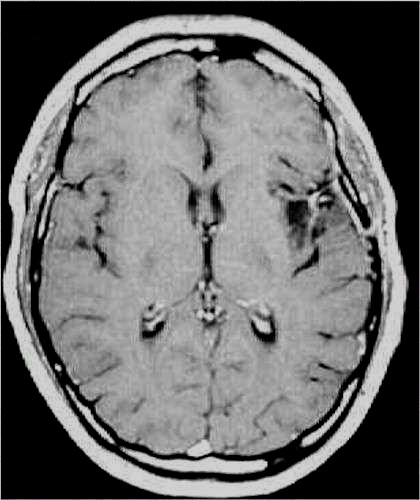

RM:

glioma con segni di trasformazione maligna

Lesioni caratterizzate da un accrescimento veloce con infiltrazione del tessuto cerebrale attiguo e diffusione a distanza di cellule maligne.

Scopo della chirurgia è ridurre macroscopicamente la massa tumorale per facilitare ulteriori trattamenti (principalmente radio - chemioterapia mentre altri protocolli terapeutici sono ancora in fase di studio).

In queste lesioni la loro conformazione anatomica, praticamente sempre di tipo II (Daumas-Duport) non ha un ruolo così dirimente nell'indicazione chirurgica poiché il comportamento biologico è sicuramente il fattore più importante.